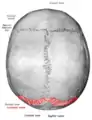

![]() Lambdoid suture (shown in red line) | |

The lambdoid suture (or lambdoidal suture) is a dense, fibrous connective tissue joint on the posterior aspect of the skull that connects the parietal bones with the occipital bone. It is continuous with the occipitomastoid suture.

The lambdoid suture is between the paired parietal bones and the occipital bone of the skull. It runs from the asterion on each side.

The lambdoid suture is named due to its uppercase lambda-like shape.